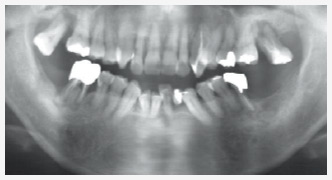

歯周病レントゲン写真

骨が細く、薄い状態になっています